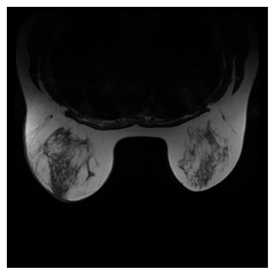

Breast-MRI-NACT-Pilot is an MRI-type image database, collecting breast medical images of 64 patients. Some samples are shown in Figure 12a.

Figure 12.

Sampled images in the tested benchmark databases: (a) Breast-MRI-NACT-Pilot (breast), (b) ACRIN-DSC-MR-Brain (brain), (c) NIH (chest), (d) Lung-PET-CT-Dx (lung), (e) Prostate-MRI (prostate), and (f) Other grayscale standard images.

- Prostate-MRI Database (available at: https://wiki.cancerimagingarchive.net/display/Public/PROSTATE-MRI (accessed on 4 November 2021))

Prostate-MRI database contains MRI-type medical images and collects prostate medical images. Some samples are shown in Figure 12e.